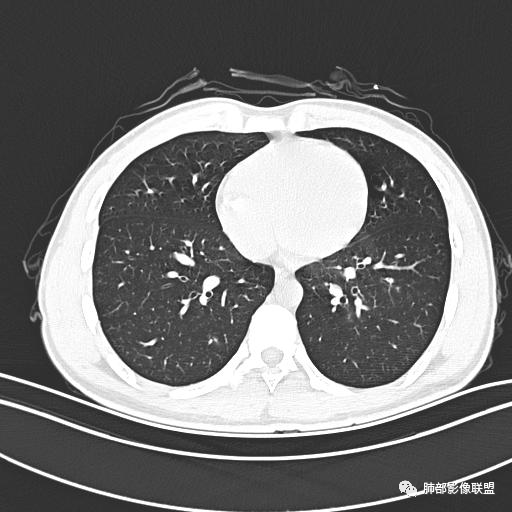

男,19岁

主  诉:发热、全身皮疹2天。

现病史:患者源于2天前受凉后出现发热,最高体温为38.5℃,且颜面部出现少量皮疹,无鼻塞、流涕、咳嗽、咳痰,未在意而未作特殊处理,次日全身皮疹逐渐增多至全身,伴轻度瘙痒,在当地卫生所给予抗病毒、抗感染治疗(具体用药不详)体温有所下降,但皮疹无明显消退,无腹痛、头痛,食欲无明显减退,为进一步诊治,遂于今日急来我院求治,患者目前精神尚可,体力正常,食欲正常,睡眠正常,体重无明显变化,大便正常,排尿正常。

小强:青年,发热,皮疹;双肺散在结节,周围磨玻璃,点晕征,疱疹病毒感染,鉴别荚膜组织胞浆菌,结核。 大雄:青年,急性起病,发热伴全身皮疹2天,抗病毒治疗体温有下降。双肺随机分布大小不等类圆结节,“点晕征”。考虑水痘-疱疹病毒(VZV)血播询问接触史,查体皮疹分布以及形态基本可诊断。 王开金江津中心医院呼吸科:青年男性,起病急,病程短,以发热,皮疹为首发症状,感染指标以单核细胞升高为主,胸部ct双肺多发结界,周围有晕,点晕表现,随机分布,同意於老师意见,水痘疱疹病毒血流感染累及肺。 王秀仙:双肺多发大小不等结节,周围有晕,边缘模糊,呈点晕征表现。青年,急性起病,发热伴全身皮疹2天,抗病毒治疗体温有下降。考虑疱疹病毒。鉴别荚膜组织胞浆菌。 傅昌瑜:19岁男性,发热、全身皮疹2天,单核细胞增高,双肺多发结节,结节边缘见边界不清磨玻璃影。点晕征+发热、全身皮疹+单核细胞增高——考虑水痘-带状疱疹病毒肺炎。 一切∮随缘:年轻男性,发热,皮疹两天,实验室,CRP,PCT增高,影像:双肺多发散在磨玻璃结节,边界欠清,大小不等,呈点晕征改变,以血管束周围分布为主,局部血管束略增粗,其它无明显改变,考虑:1:病毒性肺炎(水痘疱疹病毒?不知道皮肤有无改变)2:真菌(组织胞浆菌,血管侵袭性肺曲霉)3:GPA4:寄生虫(实验室没有看到嗜酸细胞增高) 赵山河:双肺散在结节,周围有晕,边缘模糊,呈点晕征表现。青年,急性起病,发热伴全身皮疹2天,抗病毒治疗体温有下降。考虑水痘—疱疹病毒感染。洪桥爱:青年男性,发热、皮疹2天,伴瘙痒,皮疹于面部首发,之后进展至全身,虽然没有对皮疹进行描述,但是从出疹时间及皮疹进展情况,伴瘙痒,应该就是个水痘患者;CT提示双肺随机分布结节影,部分结节伴有边界不清晕征,考虑水痘血播肺。 刘强:年轻男性,急性起病,皮疹,发热,抗感染治疗体温下降,说明有效。影像表现为散在点晕征,感染类疾病谱(疱疹病毒,真菌,结核),结合年龄,皮肤皮疹,考虑水痘-疱疹病毒性肺炎。 小兜:男性,19岁,发热皮疹两天,颜面部至全身,CRP,降钙素及单核增高。CT示双肺散在小结节,周围伴磨玻璃影,点晕征,考虑为水痘-带状疱疹病毒(varicella-zoster virus,VZV)肺炎 必有路:青年,皮疹+发热+“点晕征”→水痘-疱疹病毒(VZV) 许慧良:青年男性患者,发热、皮疹2天,体温最高38.5℃,第3天皮疹扩展至全身,伴瘙痒,胸部CT:双肺多发随机分布的小结节,结节周边见边界模糊的晕征,考虑水痘病毒感染流心明智:男,19,急性起病,发热伴全身皮疹2天。出疹顺序头→全身,抗病毒有效。胸部CT:两肺多发大小不等类圆形实性小结节影,随机分布,结节周围环绕GGO,边界模糊,呈点晕征。出疹特点是关键,未提示。考虑:血播病毒性肺炎,水痘-疱疹病毒?麻疹?鉴别荚膜组织胞浆菌、TB、血管炎、寄生虫等。 浪迹天涯:病灶多为5-10mm大小结节,结节周围可见磨玻璃样的晕环,常多发,可分布于肺内任何区域,考虑水痘—带状疱疹病肺炎如果短时间内有新的一个区域浸润,更加能说明,